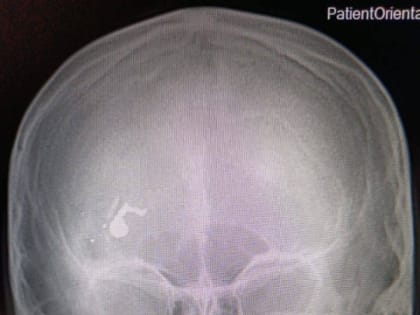

12-летний мальчик получил огнестрельное ранение в Дергачах

Медицинская помощь была оказана незамедлительно, и ребенок пришел в сознание.